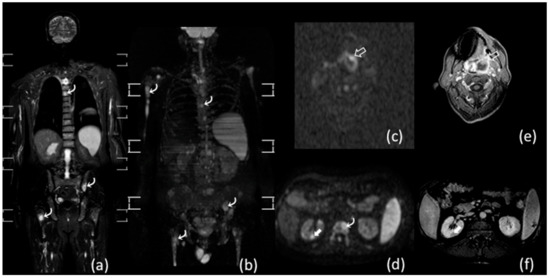

- Albano, D.; Patti, C.; La Grutta, L.; Agnello, F.; Grassedonio, E.; Mulè, A.; Cannizzaro, G.; Ficola, U.; Lagalla, R.; Midiri, M.; et al. Comparison between whole-body MRI with diffusion-weighted imaging and PET/CT in staging newly diagnosed FDG-avid lymphomas. Eur. J. Radiol. 2016, 85, 313–318. [Google Scholar] [CrossRef] [PubMed]

- Albano, D.; La Grutta, L.; Grassedonio, E.; Patti, C.; Lagalla, R.; Midiri, M.; Galia, M. Pitfalls in whole body MRI with diffusion weighted imaging performed on patients with lymphoma: What radiologists should know. Magn. Reson. Imaging 2016, 34, 922–931. [Google Scholar] [CrossRef]